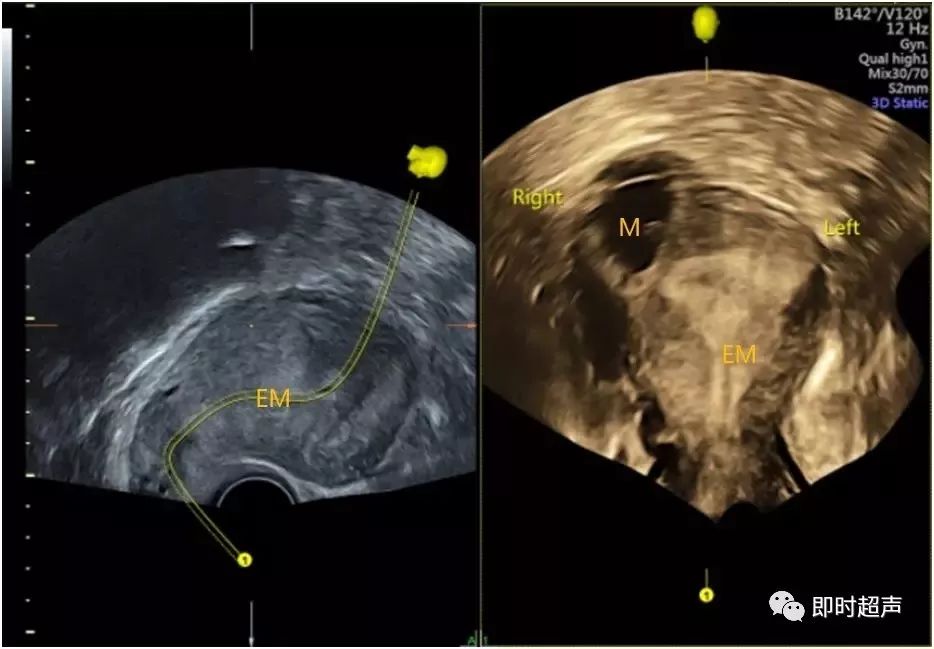

一例典型的宫内合并输卵管间质部妊娠b超征象.

图片尺寸1040x780